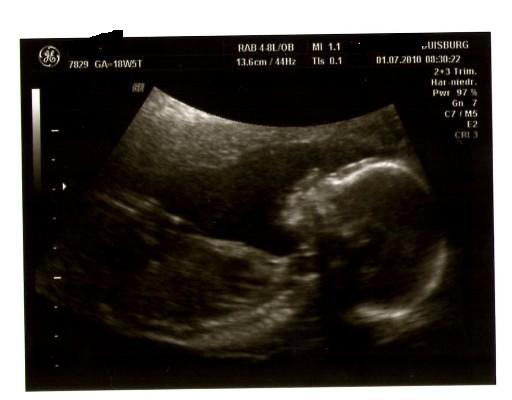

@conny: Ich stell mal gleich ein Bildchen von unserer Madame rein.Ich wollte getsren eigentlich schon aber war mir doch sehr unsicher da hier leider wieder ein paar negativs reingeflattert sind!